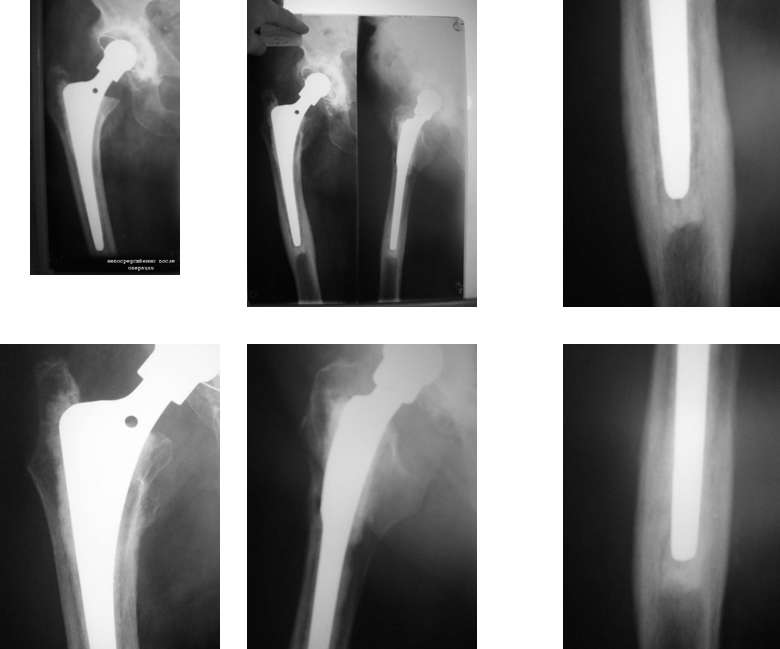

Уважаемые коллеги, у больной после цементного эндопротезирования т/бедренного сустава в течении 1.5 лет сохраняются боли при нагрузке от крыла подвздошной кости до с\3 бедра.

На Ro обнаружен периостит у верхушки ножки эндопротеза. Лейкоциты - 5,6; соэ - 11; С-реакт белок - 22.